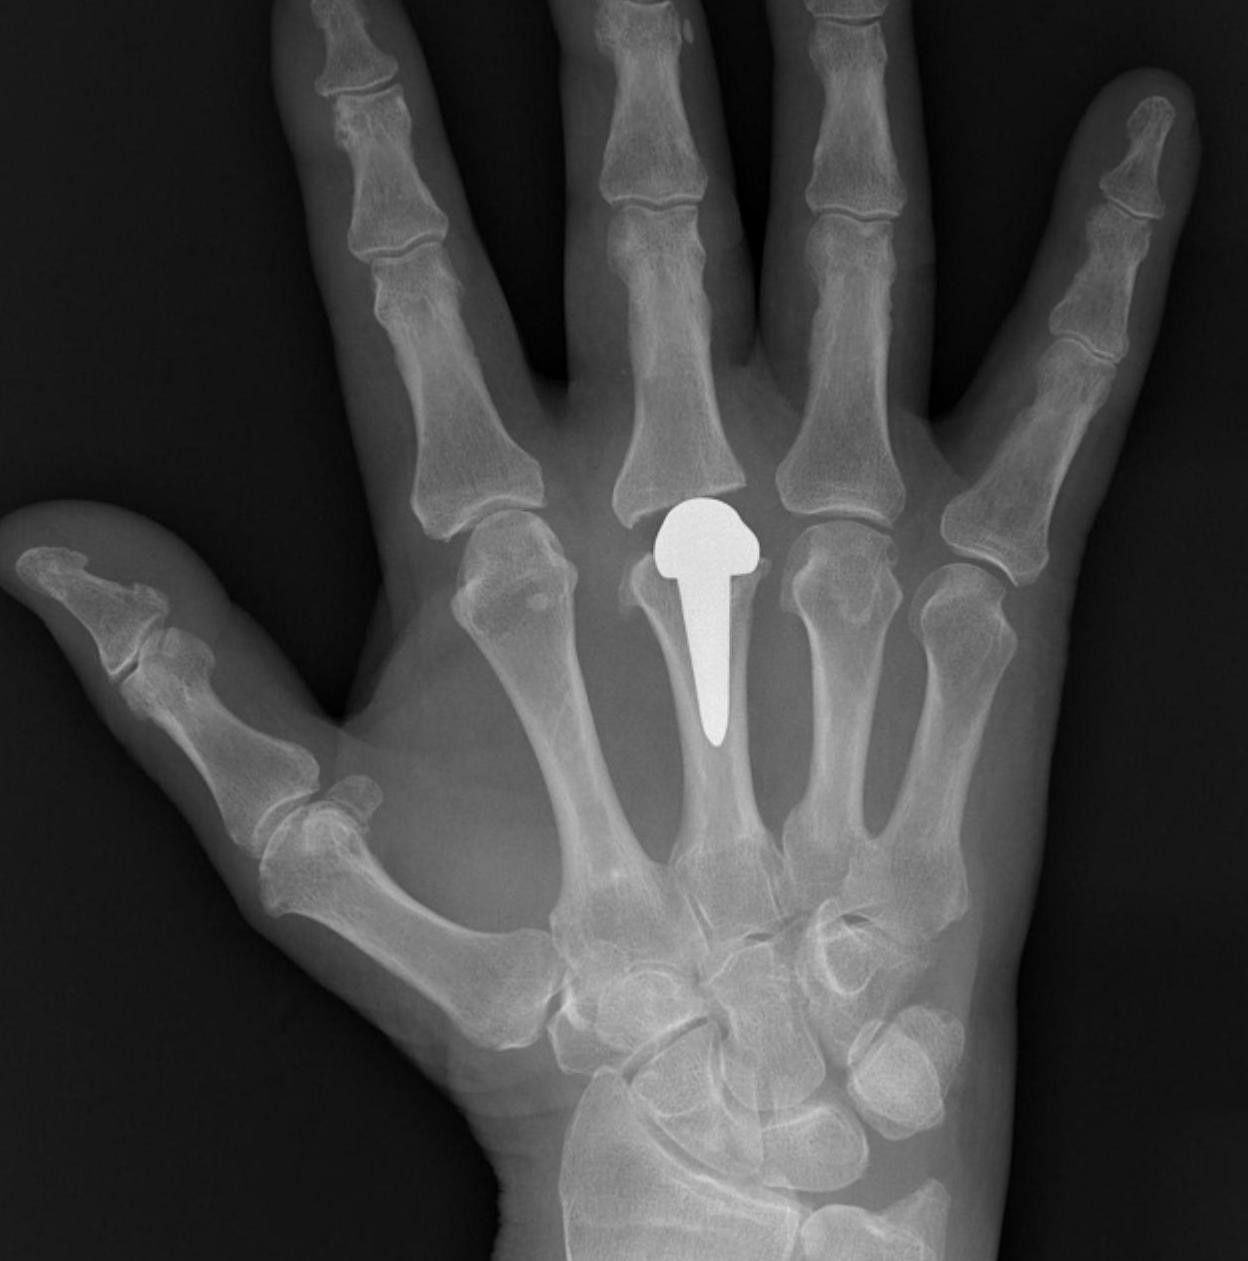

MCPJ Destruction

Cause

- infection

- trauma

Options

- joint replacement

- fusion